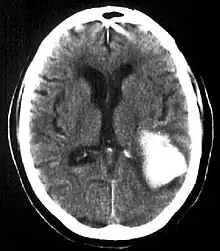

![]() | |

| Multiple intraparenchymal hemorrhage | |

Intraparenchymal hemorrhage (IPH) is one form of intracerebral bleeding in which there is bleeding within brain parenchyma. The other form is intraventricular hemorrhage (IVH).[1]